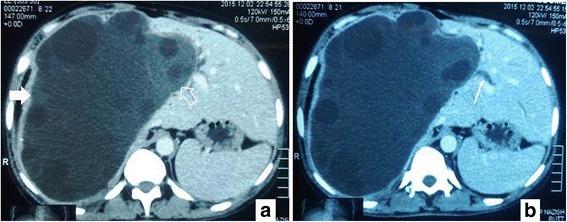

All of these cases were resected with the clinical and/or radiological impression of simple liver cysts and/or hydatid cysts. Out of the six patients, five were female and one was male. Ages of the patients ranged from 28 to 60 years (mean 45 years). The patients presented with nonspecific symptoms. Internal septations were seen on preoperative imaging (when available). On gross examination, all tumors were cystic; their sizes varied from 5.5 to 14 cm, mean size was 9.0 cm. On histopathologic examination, cystic spaces were lined by cuboidal to columnar mucin-secreting epithelium with underlying ovarian-type stroma. In one case, ovarian-type stroma was not seen. Recurrence was seen in three cases at 1 to 5 years of follow up.